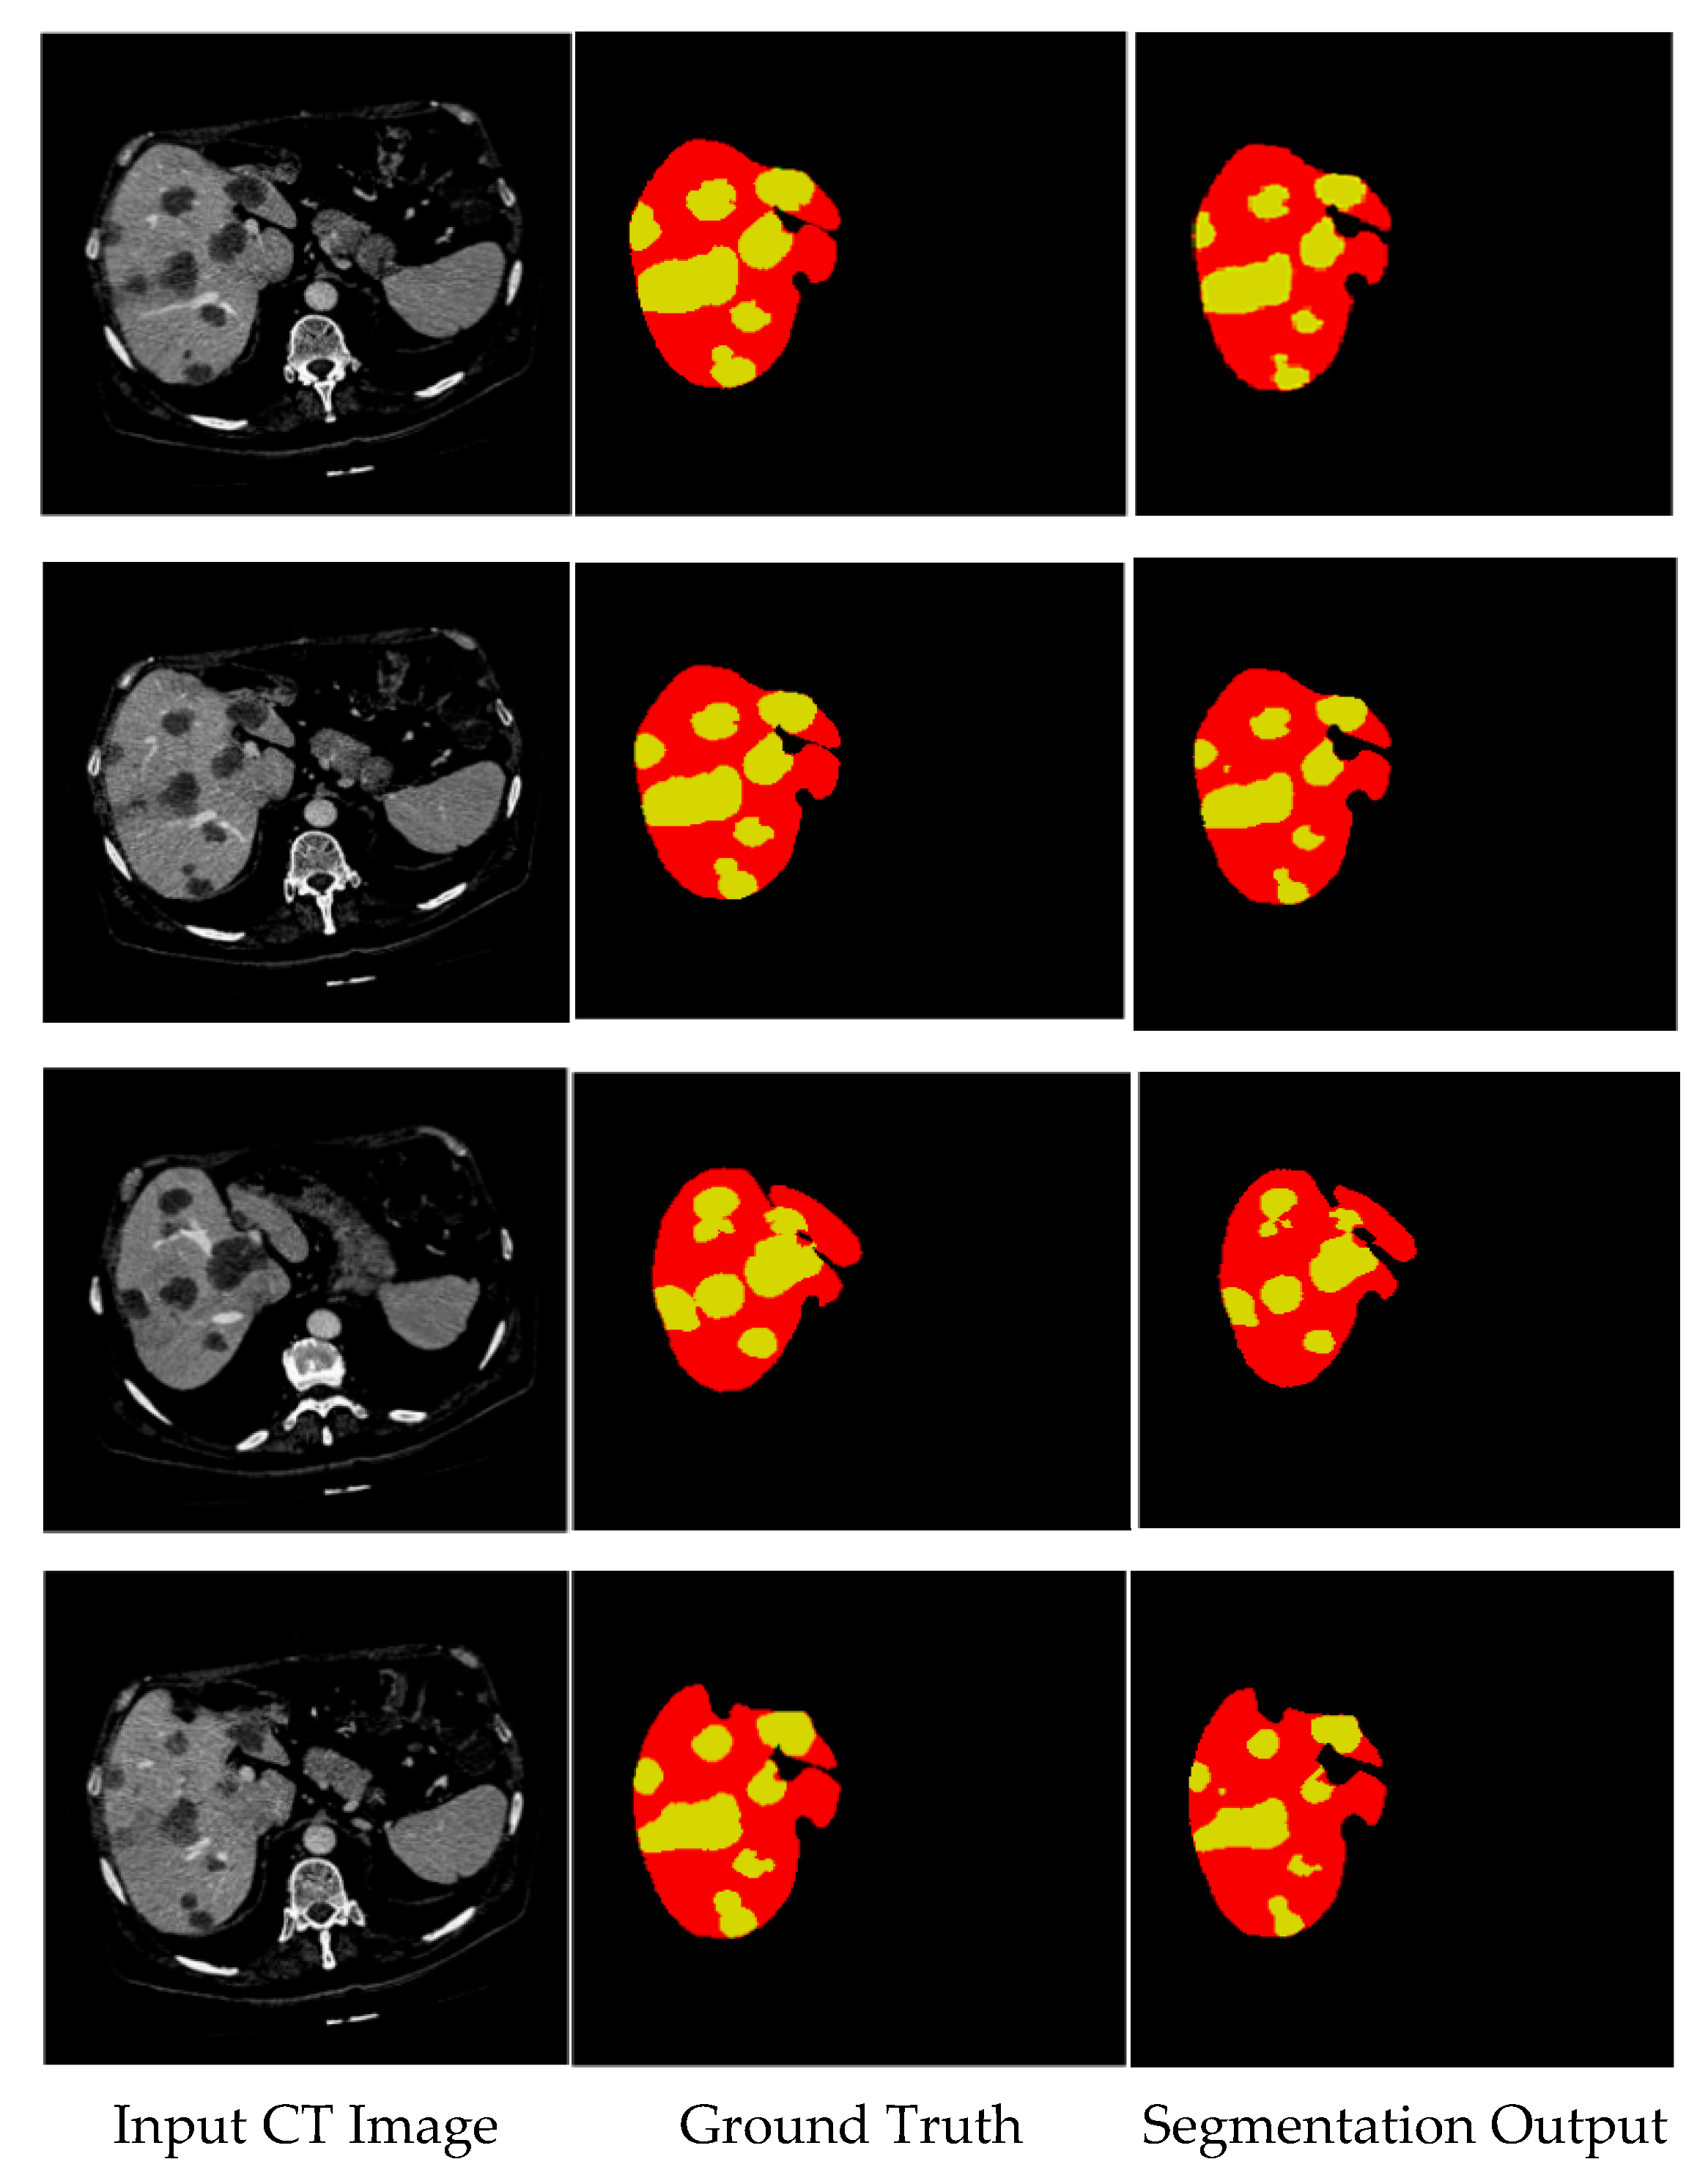

The segmentation results accurately depict the edges of the liver and tumor regions, which is crucial for defining the shape and size of these structures. The segmented areas closely align with the ground truth images, ensuring that the boundaries of the liver and tumor are well defined. This precise outlining indicates that the segmentation process was performed accurately, with no significant deviations from anatomical features. In Figure 9, the liver is shown in red, while the tumor is highlighted in yellow. Both regions are detected smoothly, without abrupt changes, demonstrating the effectiveness of the proposed system in identifying and segmenting the liver and tumor.

In Figure 10, a comparison is presented between the input images and their corresponding segmentation results. The liver is visually represented in purple, while the tumor is highlighted in pink. The segmentation results demonstrate the algorithm’s effectiveness in accurately identifying and distinguishing between the liver and tumor regions within the CT images. This visual analysis underscores the robustness of the proposed method in handling complex anatomical structures.

Figure 9. Segmentation output of proposed model for 3DIRCADb dataset.

Figure 10. Visual segmentation results of proposed model.